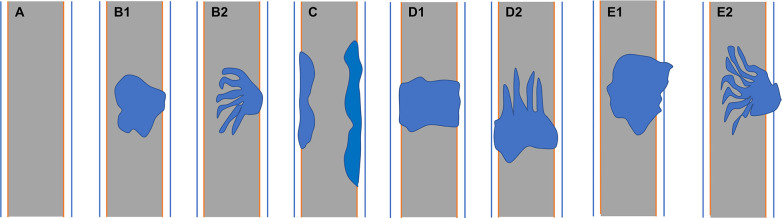

Two senior board-certified abdominal radiologists (with 7–10 years of experience) blinded to the clinical information retrospectively reviewed the abdominal MR images. Conclusions were arrived at by consensus. The radiologists recorded the 1) lesion location; 2) lesion morphology (focal eccentric-type mass, plaque-like mass, bile duct casting mass, or infiltrative mass, i.e., invasion of the bile duct muscle layer or growth out of the duct; f1); 3) growth pattern; 4) signal intensity on T1WI, T2WI, and DWI (hyperintense, hypointense, or isointense as compared to the signal intensity of normal liver parenchyma); 5) enhancement degree of the adenoma in the phase with the highest degree of reinforcement (slight enhancement, moderate enhancement, or obvious enhancement as compared to that of normal hepatic parenchyma); 6) enhancement pattern (stable and persistent, wash-in and wash-out, or progressive reinforcement); and 7) appearance types of the bile duct.

Mean lesion size in the whole sample was 30.83 ± 20.93 mm. All patients presented with an intraluminal ductal mass. While 14/32 (43.75%) lesions presented morphologically as focal eccentric-type masses (f3), 9/32 (28.13%) presented as plaque-like masses, 4/32 (12.50%) as bile duct casting masses, and 5/32 (15.62%) as infiltrative masses. In addition, 8/32 (21.88%) lesions showed a frond-like superficial appearance accompanied by other morphologically categorized appearances other than plaque-like superficial (f4, f5; T2).

Anum et al. classified intraductal papillary neoplasm of the bile duct (IPNB) morphologically as intraluminal polypoid, patellar, invasive, or lobulated with mural nodules (ref. 8). Struyve et al. (ref. 16) reported that bile duct adenoma is accompanied by bile duct dilatation with multiple irregular filling defects. However, the expression of bile duct adenoma morphology might be incomplete due to the small number of previous cases. In our patients, bile duct adenoma presented as intraductal focal eccentric-type mass, plaque-like mass, bile duct casting mass, or infiltrative mass. Bile duct adenoma presenting as a bile duct casting mass has not been previously reported. Interestingly, we found that two growth morphologies could simultaneously occur in the same patient. There have been earlier reports of bile duct adenoma with frond-like appearance (ref. 17). In this study, the superficial frond-like appearance was seen in a few lesions (25%) other than plaque-like lesions.